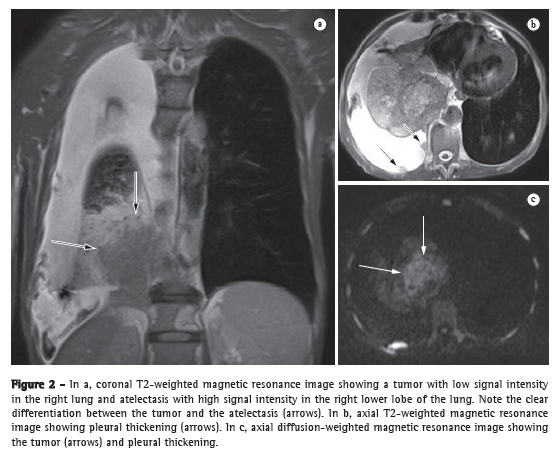

Licença Creative Commons

In patients with PH, ECG can show increased P wave amplitude (≥ 2.5 mm in the DII derivation), signs of right ventricular hypertrophy, right bundle branch block, right QRS axis deviation, and repolarization changes (right ventricular strain). Although a deviation greater than 100° has been shown to correlate well with hemodynamic measurements, its specificity for the diagnosis of PH has been shown to be low. Up to 13% of the patients with a diagnosis of PH confirmed by right heart catheterization (RHC) can initially present with normal ECG results (Figure 1).(3)

A chest X-ray reveals hilar enlargement that reflects pulmonary artery (PA) dilation and cardiomegaly. Chest X-rays also play an important role in the diagnosis of other diseases, such as those that impair the lung parenchyma and can cause dyspnea (Figure 2a).

Computed angiotomography of the chest plays a significant role in the diagnostic evaluation of PH. The diameter of the PA trunk is significantly larger in patients with PH than in normal individuals and correlates well with PA pressure measurements.(4) Studies have shown that the diameter of the PA ranges from 32.6 mm to 33.2 mm in normal individuals. One group of authors found that a PA diameter > 33.2 mm has a 95% specificity for the diagnosis of PH (Figure 2b).(5)

Magnetic resonance imaging

Advances in the techniques for acquiring and processing magnetic resonance imaging of the heart have allowed three-dimensional evaluation of the RV and detailed tomographic visualization of its morphology. Cardiac magnetic resonance imaging (CMRI) creates a clear distinction between the myocardium and intracavitary blood, presenting well-defined myocardial and endocardial borders.(8) Because the RV presents the aforementioned particularities and CMRI allows a more detailed visualization of the RV, CMRI is currently considered the gold standard for a noninvasive evaluation of the RV.(9,10) Studies in which CMRI was used to evaluate patients with PH showed that, when compared with control group patients, PH patients presented with a significant increase in end-systolic and end-diastolic volumes, as well as in right ventricular muscle mass, together with a significant reduction in right ventricular ejection fraction. Other studies have shown ventricular septal bowing, together with a reduction in the LV volume in early diastole, revealing impaired left ventricular function associated with right ventricular dysfunction.(11) One group of authors demonstrated that the position of the septum, as determined by calculating its shift toward the LV, was accurate in predicting right ventricular systolic pressure.(12) Even without the use of contrast enhancement, CMRI allows excellent visualization of the PA, and it is possible to assess PA compliance and flow by means of the phase-contrast technique. In patients with PH, PA compliance values are significantly lower.(13) One study showed that measurements of pulsatility (which is related to compliance) can also correlate with the response to the NO test.(14) The measurement of PA velocity and the time it takes to reach the maximum velocity (acceleration time) are reduced in patients with PH, and these measurements are related to systolic volume as measured by RHC.(15) In addition, CMRI plays a role in the follow-up of patients with PH. Two studies used CMRI before treatment initiation and 6-12 months after treatment initiation. In one of the studies, the patients received epoprostenol, and in the other, they received bosentan.(16,17) In both studies, improvement in the six-minute walk test (6MWT) was significantly related to improvement in right ventricular function parameters, as determined by CMRI. In another study, CMRI was used before and after pulmonary thromboendarterectomy.(18) The study showed a significant reduction in myocardial mass, right ventricular end-systolic volume, and right ventricular end-diastolic volume, as well as increased left ventricular volumes, reflecting the reversion of ventricular remodeling and septal deviation, hemodynamic improvement having been achieved with the surgical procedure (Figure 2c).